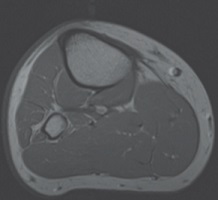

• Lower Leg by MAJOR / Musculoskeletal Anatomy